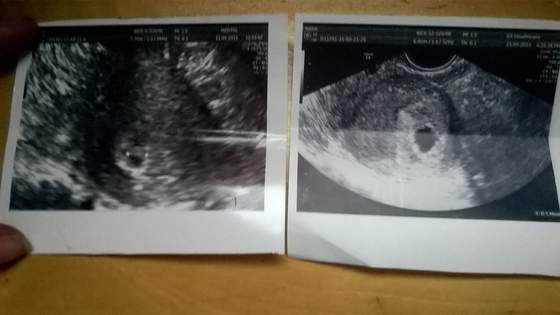

dodam ze te pierwsze usg to myslalam ze jestem w prawie 7 tyg a ciaza jest mlodsza o ok tydzien do dwoch tyg glowa do gory